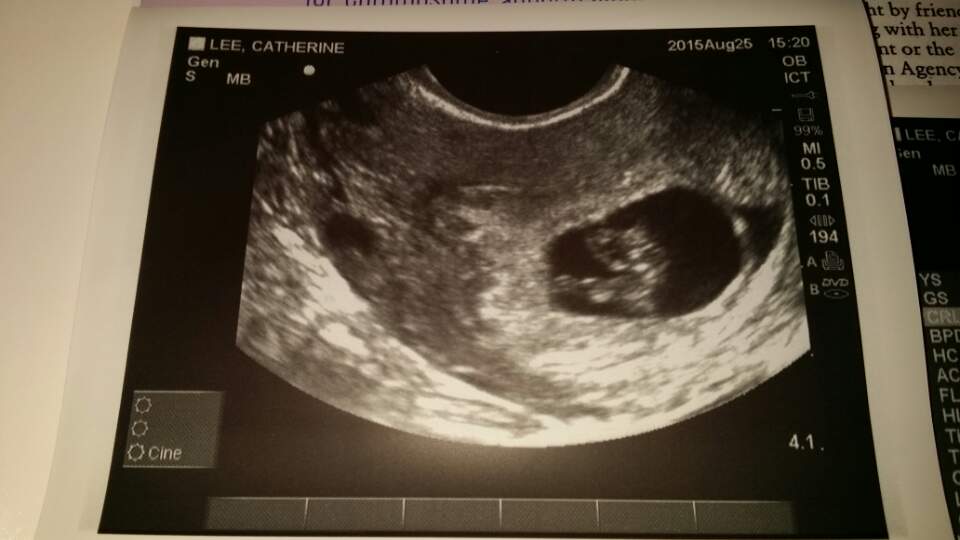

Had an unexpected US today due to some cramping. I was so expecting the worst... I am my own worst enemy but, baby has once again doubled in size from last Friday 8.21.15 to today 8.28.15!! Heartbeat today was up from 165 to 182!!!! We also got to see he/she wiggle which brought tears to my fiancées eyes... And in turn I cried. Tears of joy!! Keeping all of you in my thoughts! Positive vibes your way!